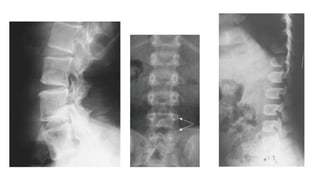

SPONDYLOEPIPHYSEAL DYSPLASIA TARDA

• Short stature-due to platyspondyly,

• Hyperostosis of posterior 2/3rd of

heaping up vertebra

• Bilateral flattened femoral heads,

SPONDYLOEPIPHYSEAL DYSPLASIA TARDA •X linked recessive- only in males • 5-10 years of age • Short stature-due to platyspondyly, more marked in thoracic region • Hyperostosis of posterior 2/3rd of vertebral bodies- hump shaped/ heaping up vertebra

• Bilateral flattenedfemoral heads, short necks and premature degenerative changes • Small pelvis with mild-to-moderate epiphyseal irregularity leading to early osteoarthritis at hips